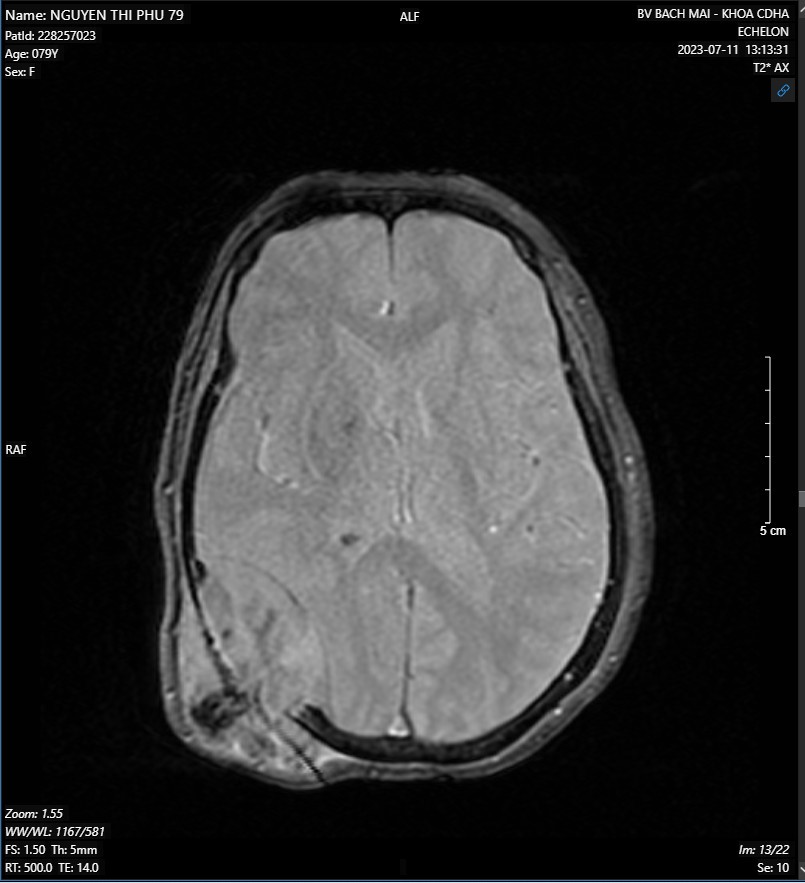

- MRI não-mạch não có tiêm thuốc đối quang từ:

Hình ảnh khối ngoài trục vùng thái dương-chẩm phải kích thước 48x50x60mm nghĩ nhiều đến khối u xương, có chảy máu trong u, gây tiêu xương sọ và xâm lấn phần mềm

Hình 2. Hình ảnh MRI não-mạch não có tiêm thuốc đối quang từ.